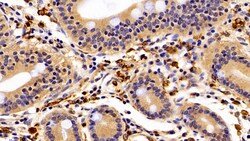

IBA1 Polyclonal Antibody for Western Blot, IHC (P)

Ionized calcium-binding adapter molecule 1 (IBA1), also known by its gene name AIF1, is a protein expressed predominantly by microglia in the brain and spinal cord. This protein belongs to the EF-hand calcium-binding protein family and plays a crucial role in microglial activation and migration in response to brain injury or neuroinflammation. IBA1's function is integral to microglial motility and phagocytic activity, facilitating the cellular response to pathogenic stimuli and promoting tissue homeostasis and repair in the central nervous system. IBA1 serves as a reliable marker for activated microglia in various neurological disorders, including Alzheimer's disease, Parkinson's disease, and multiple sclerosis, where increased expression correlates with disease progression and severity. The protein's structural features enable it to bind calcium ions, inducing conformational changes that activate signaling pathways essential for microglial function. Its expression is highly regulated by inflammatory cytokines, underpinning its role in neuroimmune responses. Due to its specific expression in microglia during pathological conditions, IBA1 is widely used in research as a marker to study microglial status and activity, and it remains a focal point for understanding microglial involvement in neurodegenerative diseases.Specifications

| Immunohistochemistry (Paraffin), Western Blot | |